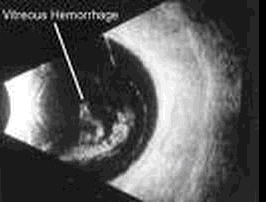

患者,女,14岁,眼部外伤2个小时。超声检查如图,最可能的诊断为 CF20160315_50.gif

• A.玻璃体积血

• B.玻璃体混淆

• C.脉络膜脱离

• D.视网膜脱离

• E.眼内异物